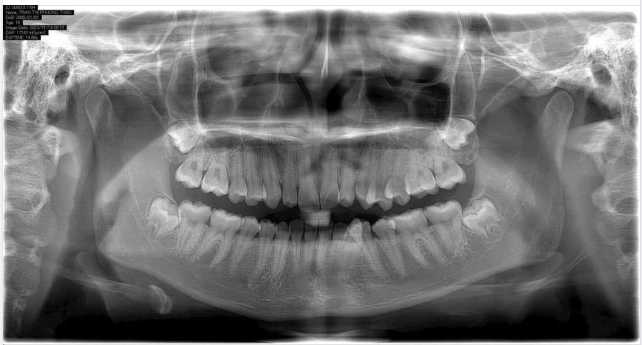

NHỔ RĂNG SỐ 8 KHÔNG ĐAU, KHÔNG PHẢI NGHỈ DƯỠNG, VỎN VẸN CHỈ TRONG 30’

? Răng 8 mọc ngầm, mọc lệch đâm vào răng số 7 gây hỏng răng số 7

? Răng 8 mọc lợi chùm gây viêm đau, há miệng khó cứng hàm

? Răng 8 khiến hàm răng xô lệch, khấp khểnh